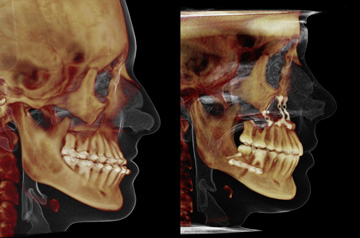

Contouring of the mandible, maxillary advancement and rhinoplasty

Primary Diagnoses

- Asymmetry of the mandible

- maxillary deficiency

- angle class III malloclusion

Orthognathic surgical treatment

- Upper Jaw Osteotomy

- Lower Jaw Osteotomy

- Rhinoplasty

- Contouring of the mandibular body

Surgery was performed in 2015 at our Face Smile Center by Dr. Andrey Senyuk, oral and maxillofacial surgeon.